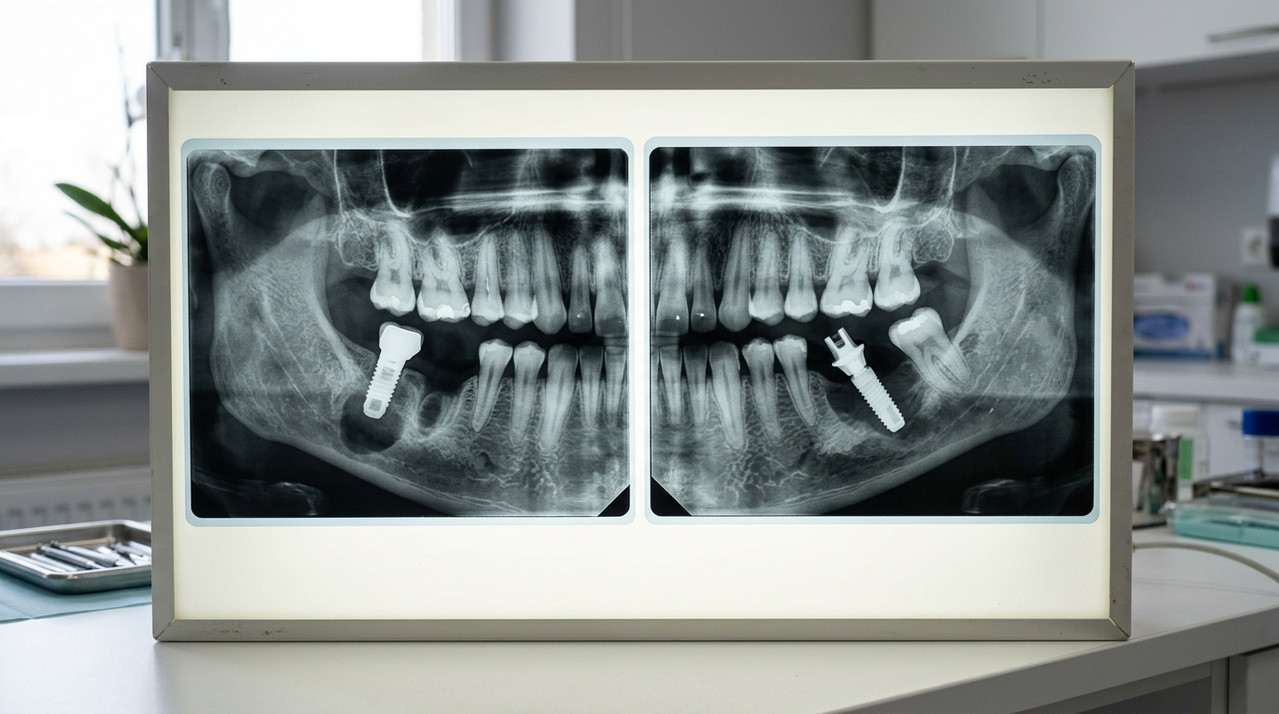

Рентгеновские снимки осложнений одномоментной имплантации: периимплантит и отторжение штифта

Примеры осложнений на рентгене и меры их предотвращения.

Риски включают периимплантит (воспаление вокруг импланта, 5–10% случаев), отторжение (2–3%), повреждение соседних зубов или нервов нижней челюсти. В России частота осложнений ниже в сертифицированных центрах — 4% по данным Минздрава 2025 года. Профилактика: строгий гигиенический контроль, отказ от курения за 2 недели до и после, правильная нагрузка.